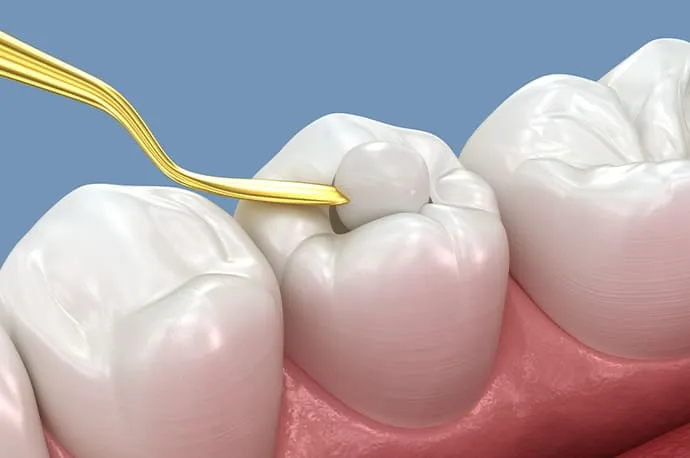

③根管貼薬

根管拡大と洗浄後、根管内にお薬を入れて一時的に封鎖します。これは、処置だけでは取りきれなかった細菌をさらに減らすことを目的としています。

根管貼薬(1回目治療終了)

ある程度消毒が完了した段階で、根管内にお薬を入れてフタをします(根管貼薬)。この状態で一度治療を終え、1~2週間ほどお薬を効かせます。

根管充填と土台作り

再来院時に問題がなければ、根管内に防腐剤の詰め物を行います(根管充填)。その後、感染を防ぐため、歯と強力に接着するレジンなどの材料で上からフタをし、歯の土台を作ります(築造)。